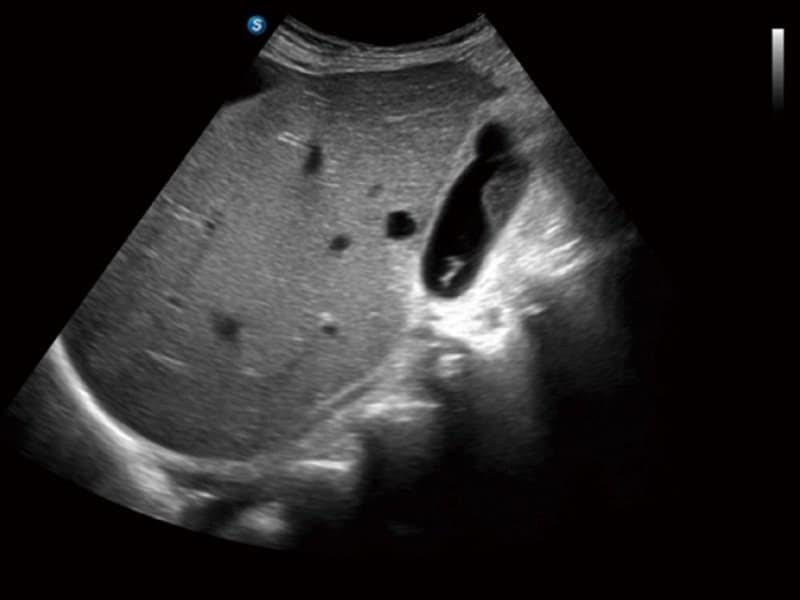

Klinische Bilder

- Radiologie: Quantitative Beurteilung der Lebersteatose durch ATI, Strain-Elastographie und kontrastverstärkter Ultraschall (CEUS)

- Gynäkologie & Geburtshilfe: Hochauflösende 3D/4D-Bildgebung sowie automatisierte Messungen wie Auto OB und Auto NT zur effizienten Vorsorge.